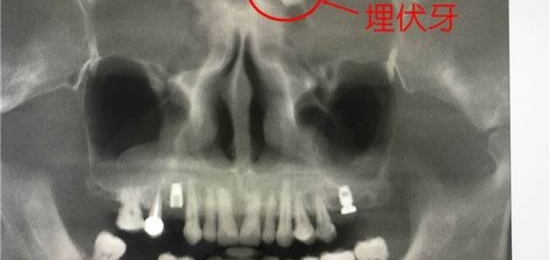

据杭州交通918频道11月9日报道,近日,深圳市某医院的口腔科出现了一件闻所未闻的的“奇事”:一名男子因为口腔问题就医,却被医生发现在眉间正中躺着一颗“牙”,而这也导致他常年鼻塞。

为了更加详细的了解病情,医生建议他拍摄CBCT。通过CBCT,医生观察到,这名患者不仅口腔状况“糟糕”,更是奇特的是,他的额头上竟然长着一颗“牙齿”。在CBCT多种功能帮助下,确定该牙位于左侧筛窦内。利用3D重建切除部分骨,便可看到该牙斜躺着。

医生介绍说,像这样在其他区域“非法生长”的牙齿,专业上叫做“埋伏牙”。在临时实践中,“埋伏牙”长在上颌窦或牙槽骨等处比较常见,而像这位患者那样长在眉间正中位置的极为罕见。